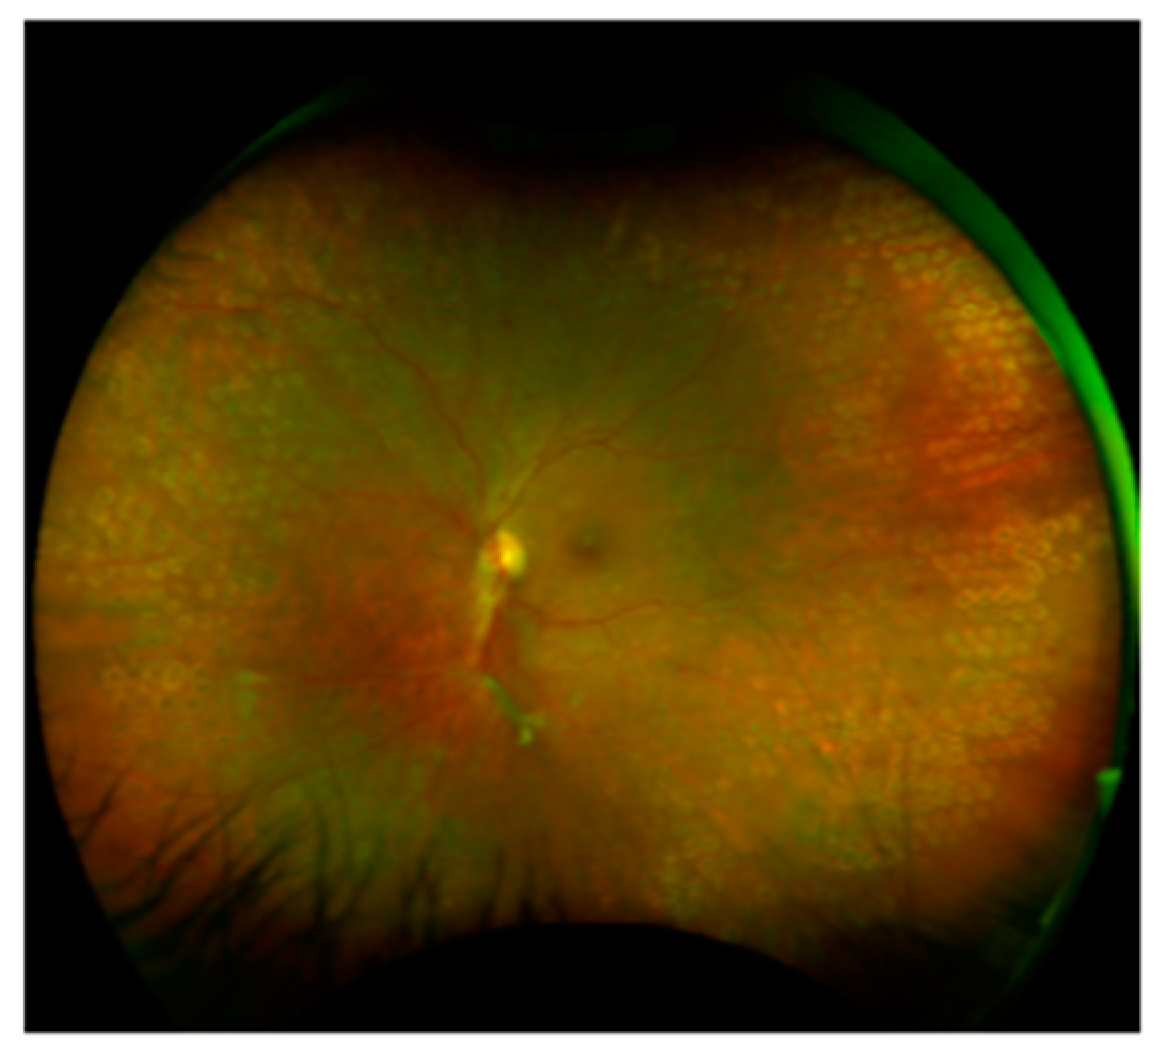

4. Clinical Profile

5. Ophthalmic Diagnostics